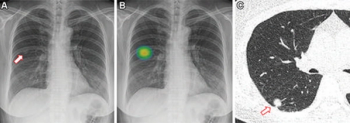

People who smoke marijuana and cigarettes have 12 times the risk for centrilobular emphysema than non-smokers, according to new computed tomography (CT) research presented at the annual Radiological Society of North America (RSNA) conference.

Artificial intelligence (AI) assessments of chest X-rays identified 28 percent of a 17,000 plus cohort of never-smokers as being at high-risk for lung cancer, according to research to be presented at the annual Radiological Society of North America (RSNA) conference next week.

Ultra-low-dose computed tomography (ULDCT) may have similar efficacy as low-dose CT (LDCT) for detecting a variety of pulmonary conditions in people with current or past smoking histories, but had poor detection of ground glass opacification lesions, according to a recent prospective study presented at the Radiological Society of North America (RSNA) conference.